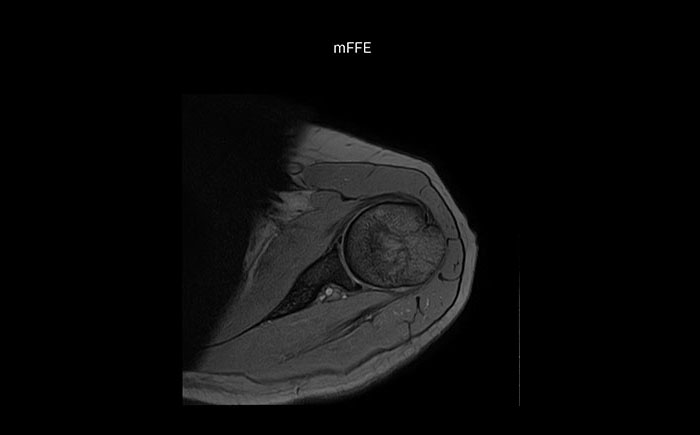

Shoulder MRI with high quality, large coverage

The Prodiva shoulder coil is very flexible and has large coverage, which makes good positioning easier, and that contributes to the superb image quality and high SNR that we get in our shoulder exams.

Scan time 2:55 min, FOV 160 mm,

acq voxels 0.55 x 0.83 x 3.0 mm.

Scan time 4:19 min, FOV 160 mm,

acq voxels 0.55 x 0.80 x 3.0 mm.

Scan time 2:50 min, FOV 160 mm,

acq voxels 0.70 x 0.99 x 3.0 mm.

Shoulder MRI with high quality, mFFE